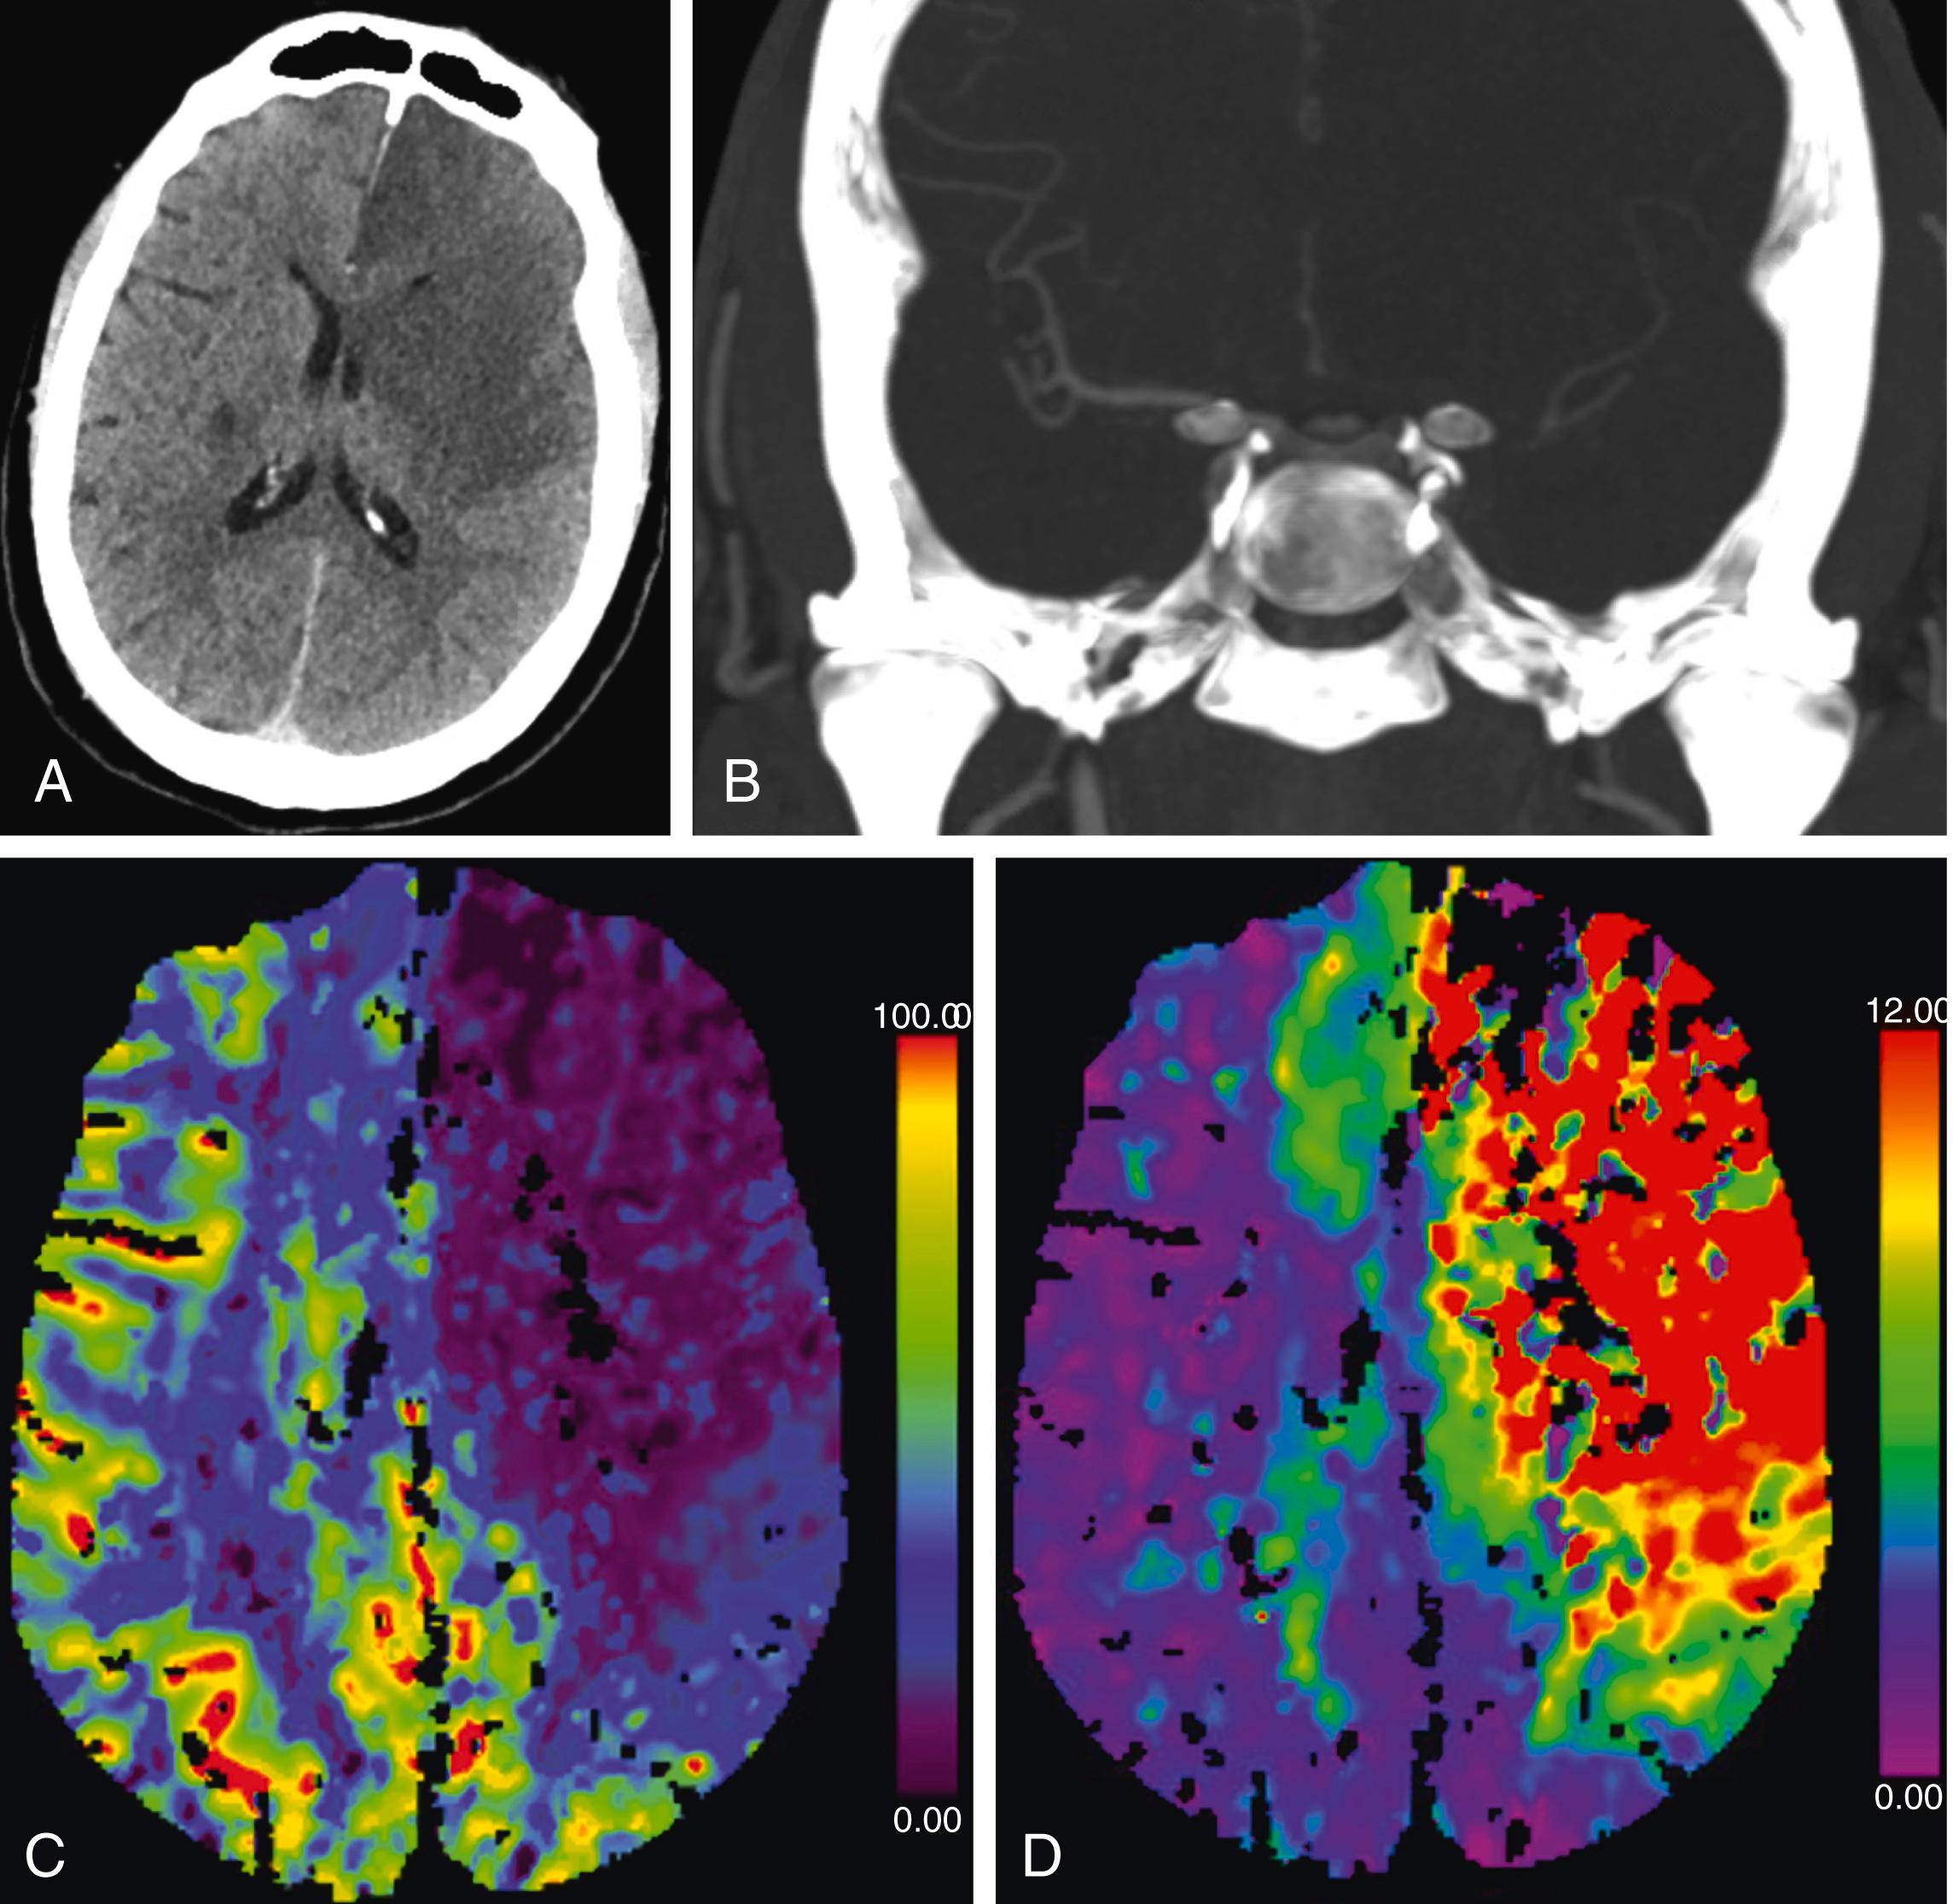

Figure 24.1, A. Initial axial head CT without contrast in the ED demonstrates a large left frontotemporal hypodensity without significant midline shift. B. Coronal maximal intensity projections of a head CTA demonstrates non-opacification of the left ICA termination. C. Cerebral blood flow color map demonstrates a large ischemic core in the left ACA and MCA territories. D. Tmax color map demonstrates almost complete overlap with the cerebral blood flow deficit, indicating minimal penumbra.

Upon arrival to the ED, the stroke team was emergently activated and a head CT without contrast showed a large area of hypodensity in the left anterior cerebral artery (ACA) and middle cerebral artery (MCA) territories concerning for acute infarction, along with 5 mm of rightward midline shift. CT angiogram (CTA) and CT perfusion (CTP) studies showed occlusion of the left internal carotid artery (ICA) terminus and absent filling of the ACA and MCA territories with a completed large core infarction ( Figure 24.1 ). Of note, the patient takes daily aspirin (ASA) 81 mg for his prior stroke, last taken one week ago per his wife.